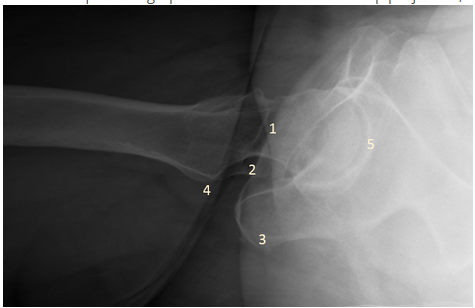

In the example radiograph below of the cross-table hip projection, which number represents the lesser trochanter?

C - 4

The labeled structures in the radiograph are identified as follows: number 1 represents the femoral neck, number 2 the greater trochanter, number 3 the ischial tuberosity, number 4 the lesser trochanter, and number 5 the acetabulum.